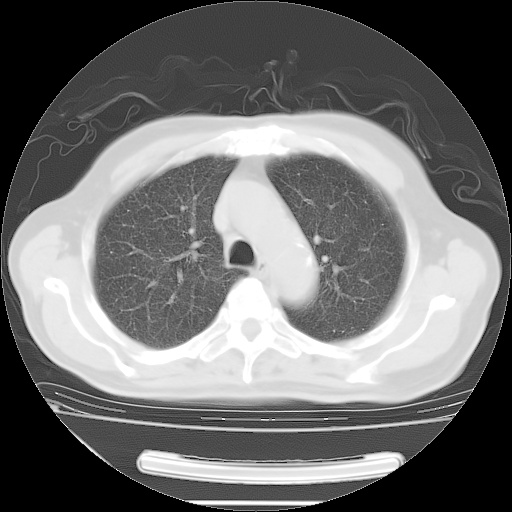

胸腹部CT,诊断意见:左上肺叶钙化灶、左侧胸膜局限性增厚并钙化、胆囊炎。描述部分肺组织呈磨玻璃样改变。